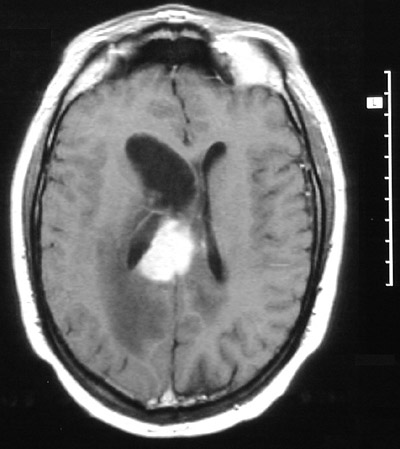

| This MRI scan of the head in axial view demonstrates an enhancing periventricular mass with prominent adjacent vasogenic edema. This is a central nervous system lymphoma. CNS lymphomas can occur in patients with AIDS but also in persons without an underlying disease state. |